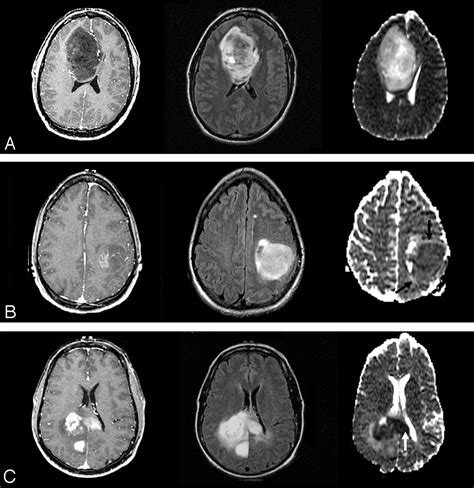

A standard Brain Neoplasm MRI protocol involves several different "sequences" or scan types. Each sequence is designed to highlight different biological features of the tissue. For example, T1-weighted images are excellent for anatomical detail, while T2-weighted and FLAIR (Fluid-Attenuated Inversion Recovery) images are highly sensitive to identifying edema or inflammation around a mass.

To improve the diagnostic accuracy, doctors often use a gadolinium-based contrast agent. When injected intravenously, this contrast material accumulates in areas where the blood-brain barrier is compromised, which is typical in many types of neoplasms. This "enhancement" helps doctors clearly delineate the tumor from healthy brain tissue.

• Diffusion-Weighted Imaging (DWI): Measures the movement of water molecules to help distinguish between different types of tumors or identify abscesses.

• Magnetic Resonance Spectroscopy (MRS): Analyzes the chemical composition of the tissue, helping to distinguish tumor tissue from radiation necrosis.

• Perfusion Imaging: Maps the blood flow volume within the tumor, which can help indicate how aggressive a tumor might be.

These advanced tools provide the neurosurgeon with a "map" of the brain, identifying functional areas—such as speech or motor cortex—that need to be avoided during surgery. This level of precision is what makes the modern Brain Neoplasm MRI an indispensable tool in neuro-oncology.

Interpreting the Results